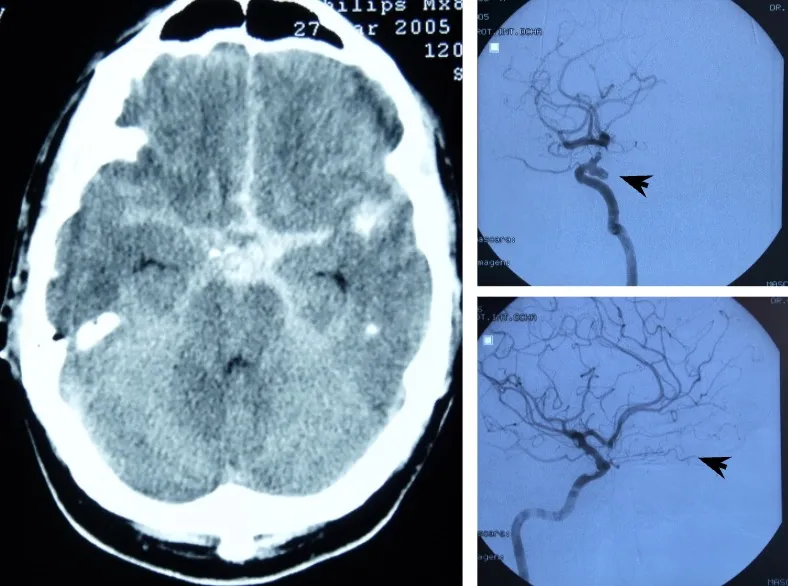

El diagnóstico se apoya en la tomografía computarizada (TAC) y la arteriografía cerebral.

El diagnóstico de la hemorragia subaracnoidea y del aneurisma causante se realiza en dos fases complementarias:

En primer lugar, se confirma la presencia de sangre en el líquido cefalorraquídeo. La prueba fundamental es la tomografía computarizada (TAC), que permite visualizar la sangre en el espacio subaracnoideo. Cuando existen dudas diagnósticas —por ejemplo, para diferenciarlo de una meningitis—, puede realizarse una punción lumbar que confirme la presencia de sangre en el LCR.

Una vez confirmada la hemorragia, es necesario identificar el aneurisma responsable. Para ello se emplean la angio-TAC (TAC con contraste vascular) y el estudio angiográfico cerebral (arteriografía), que no solo permiten localizar y caracterizar el aneurisma antes de la intervención, sino que también sirven para comprobar que el aneurisma se ha cerrado correctamente tras el tratamiento.